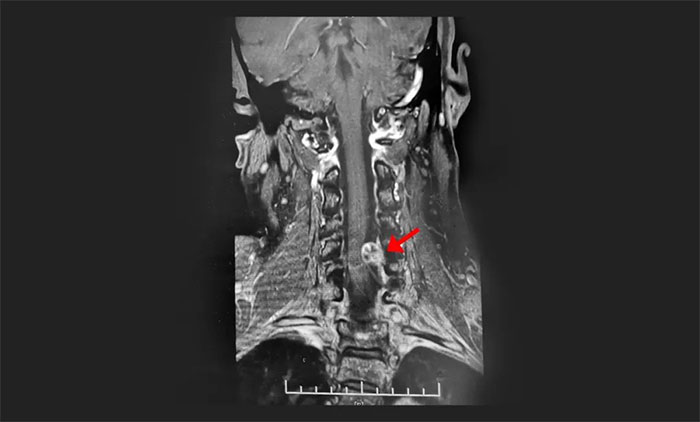

出现在人体脊髓部位的任何病症,都不是小问题。37岁的姜女士是两个孩子的母亲。2018年10月下旬,短短数天时间,从头晕恶心到全身瘫痪,再到呼吸困难生命垂危,疑似患上脊髓恶性肿瘤的诊断结果,一度让她打算料理后事。抱着最后一线希望被送进上海蓝十字脑科医...[详细]